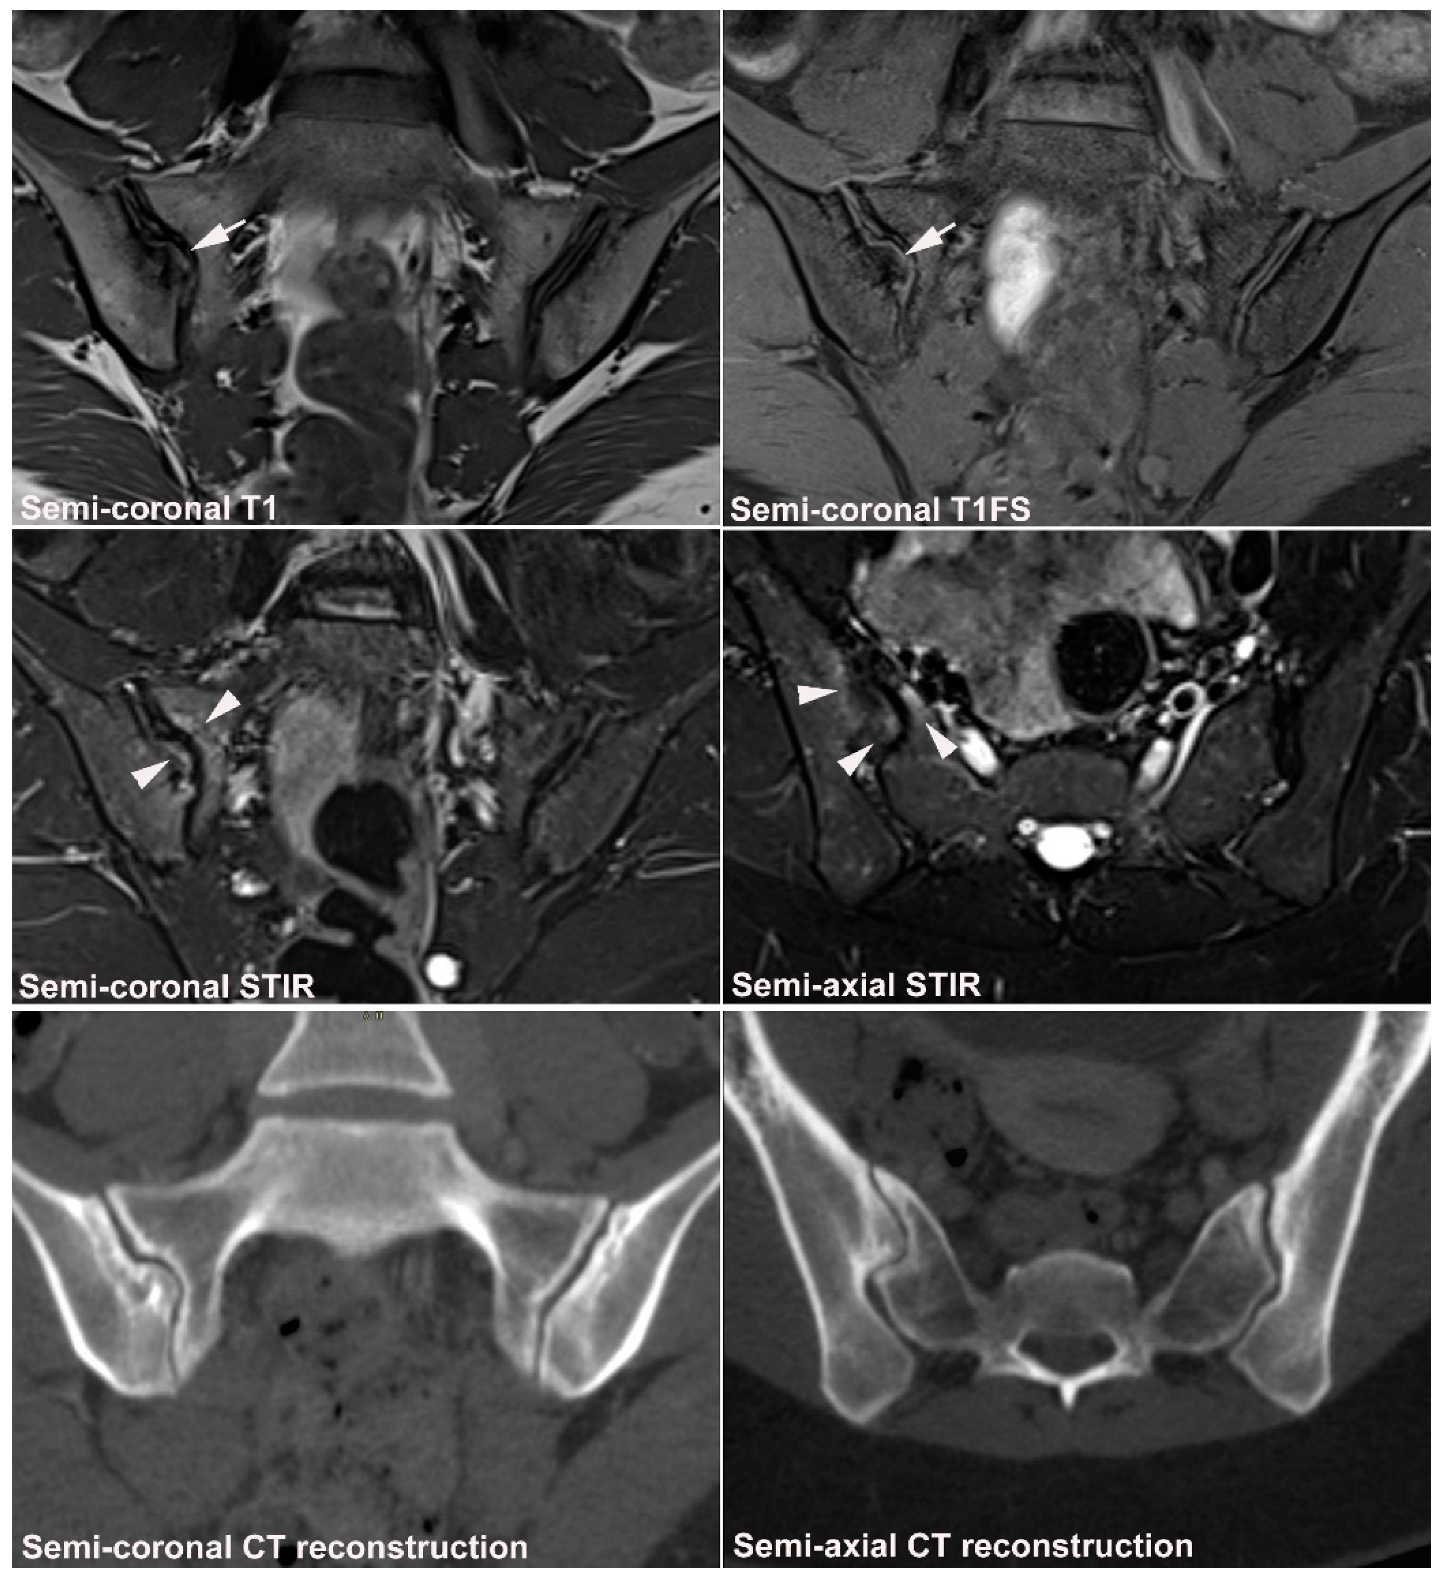

10.1. Sacral Stress Fracture

10.2. Sacral Insufficiency Fracture

- Weber, U.; Jurik, A.G.; Zejden, A.; Larsen, E.; Jørgensen, S.H.; Rufibach, K.; Schioldan, C.; Schmidt-Olsen, S. MRI of the Sacroiliac Joints in Athletes: Recognition of Non-Specific Bone Marrow Oedema by Semi-Axial Added to Standard Semi-Coronal Scans. Rheumatology 2020, 59, 1381–1390. [Google Scholar] [CrossRef]